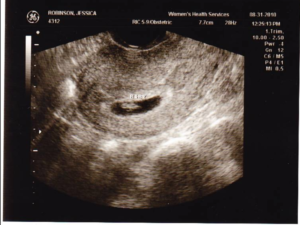

Во время УЗИ специалист обязательно должен измерить и зафиксировать копчико-теменные размеры плода, а также его положение в полости матки, состояние желтого тела, яичников и миометрия. Все эти данные позволят рассчитать размеры малыша и примерную дату его рождения.

На сроке в 5-6 недель они должны быть следующими:

- размер эмбриона – от 2 до 3 мм;

- размер желточного мешка – 4-5 мм (если он больше 6 мм, это может свидетельствовать о патологии);

- размер плодного яйца – около одного сантиметра;

- частота сердцебиения – от 70 до 100 за 60 секунд.

Других показателей на таком сроке пока быть не может.